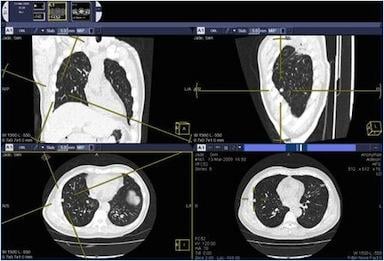

To improve radiology workflow, VTRIP is designed to allow for the more efficient reading of computed tomography (CT) and magnetic resonance (MR) studies making both the technologist and radiologists more efficient by seamlessly embedding advanced viewing, image analysis and reconstruction capabilities directly into their normal workflow.

• Multiplanar reconstructions (MPR) viewports grouped to use same W/L and zoom/pan

• Triangulation to quickly zoom to point in multiple MPR views and back